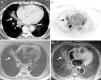

In view of the patient's history of cancer, a positron emission tomography (PET)/CT was performed. In the PET component, hypermetabolic areas were observed in the areas of lung consolidation. Parenchymal opacities with fat attenuation were observed in the CT component, so a presumed diagnosis of lipoid pneumonia was given. Since the patient refused a fiber bronchoscopy, the opacity was studied with a chest MRI that revealed hyperintensities in T1-weighted sequences, which were suppressed in fat suppression sequences (e.g. the STIR sequence) (Fig. 2). These findings were consistent with ELP.

Computed tomography (CT) axial image of the mediastinum (A) showing peribronchial opacity in the right lung with areas of fat attenuation (arrow). Positron emission tomography image (B), showing hypermetabolic areas in the right lung base, coinciding with the opacities seen on the CT (arrow). Axial magnetic resonance images, showing signal hyperintensity of the opacity in T1-weighted sequences (C) and signal suppression in the fat saturation sequence (D) (arrows).

The patient stopped using Vaseline for tracheotomy cannula care and received low dose corticosteroids. Six months later, complete radiological resolution of the opacity was confirmed.